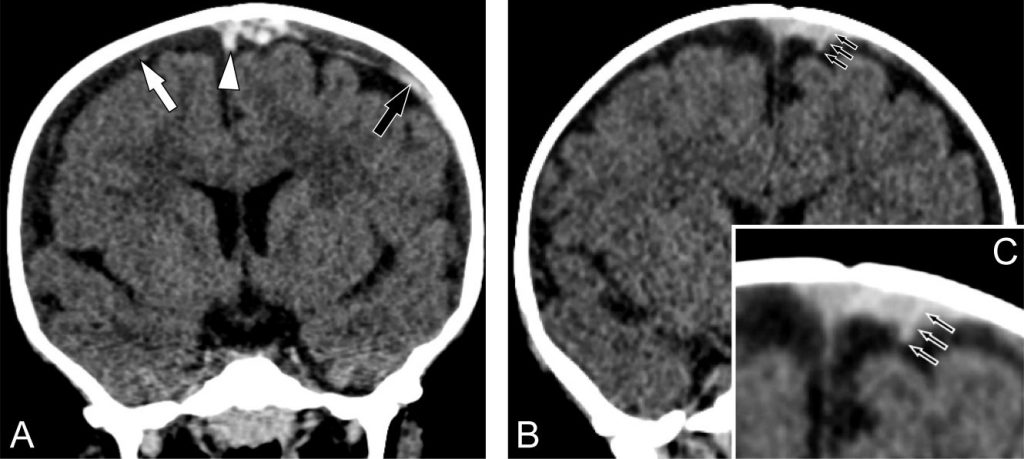

Fig. 117.1 Examen tomodensitométrique cérébral réalisé sans injection de produit de contraste en coupes coronales chez deux nourrissons ayant des troubles de la conscience inexpliqués et des hémorragies rétiniennes au fond d’œil.

Hématomes sous-duraux multifocaux (A) hypodense (flèche blanche) et hyperdense (flèche noire), thrombose d’une veine pont (tête de flèche). Thrombose de veine pont traversant un hématome sous-dural (B) avec agrandissement (C).

La lésion la plus fréquente est l’hématome sous-dural aigu. Sa localisation au vertex et le caractère multifocal sont évocateurs de secouement. La mise en évidence d’une rupture/thrombose d’une veine pont est très spécifique d’un secouement (figure 117.1). Les autres lésions à rechercher au scanner sont l’hémorragie sous-arachnoïdienne (50 %), les lésions parenchymateuses notamment ischémiques et les fractures (secouement avec impact).